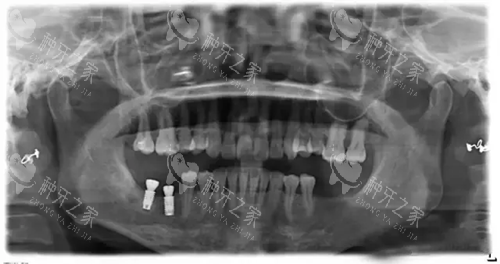

35岁女性患者,左上中切牙缺失3年,牙槽骨宽度仅3.8mm。传统方案建议先植骨再种植,治疗周期长。采用美格真3.5mm窄径植体,直接植入,未行骨增量手术。

术后4个月,种植体骨结合良好,边缘骨水平稳定。修复后牙龈形态自然,与邻牙协调一致。3年随访显示,种植体周围骨水平无显著变化,美学结果持久稳定。

狭窄间隙修复实例

48岁男性患者,下颌头一前磨牙缺失,缺牙间隙近远中距离仅6.5mm。采用美格真3.5mm窄径植体,植入后种植体与邻牙保持1.2mm可靠距离,未损伤邻牙牙根。

修复后咬合功能良好,无食物嵌塞。2年随访显示,种植体稳定,无异常松动,患者对功能与美观均满意。